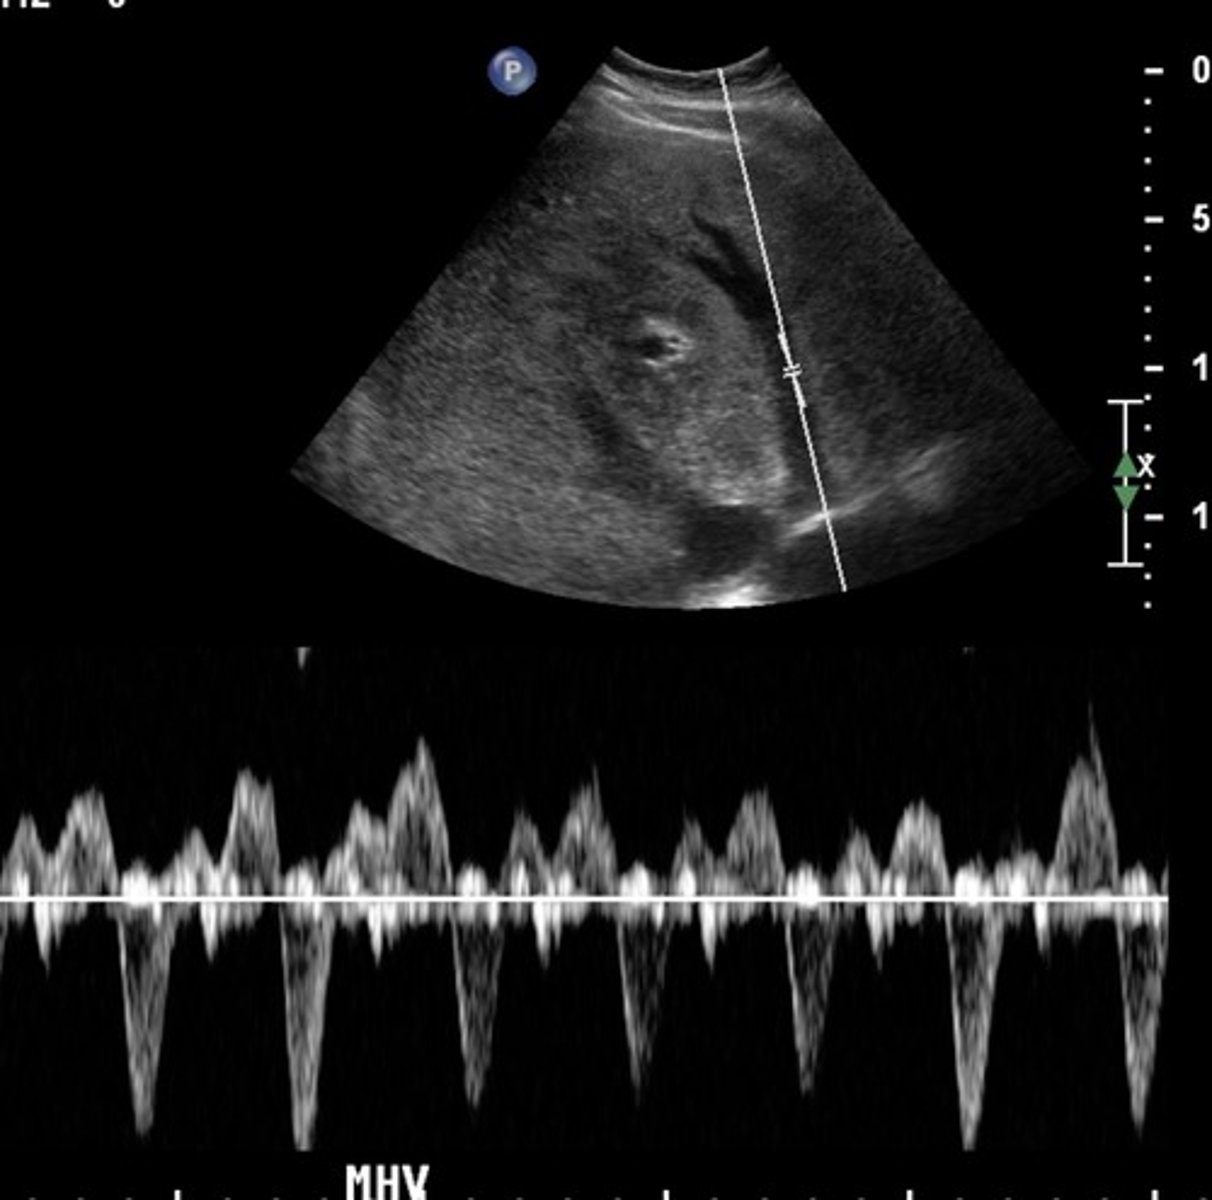

Hepatic Vein Doppler Waveform

Triphasic

Antegrade & retrograde flow - cardiac pressure changes

Hepatic Vein Doppler

S wave: ventricular systole

D wave: atrial filling

A wave: atrial contraction

Inspiration depresses systolic wave

Exhalation augments systolic wave

Valsalva diminishes pulsatility